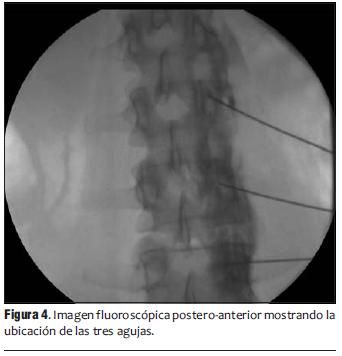

3. Procedimiento guiados a los sitios dolorosos o a estructuras nerviosas para inhibir o bloquear el dolor, conde alivió seguridad y bajo condiciones orientadas con fluroscopia (Rxs) y por medio de ultrasonido, y de vanguardia con radiofrecuencia pulsada que extienda el tiempo de semanas a años